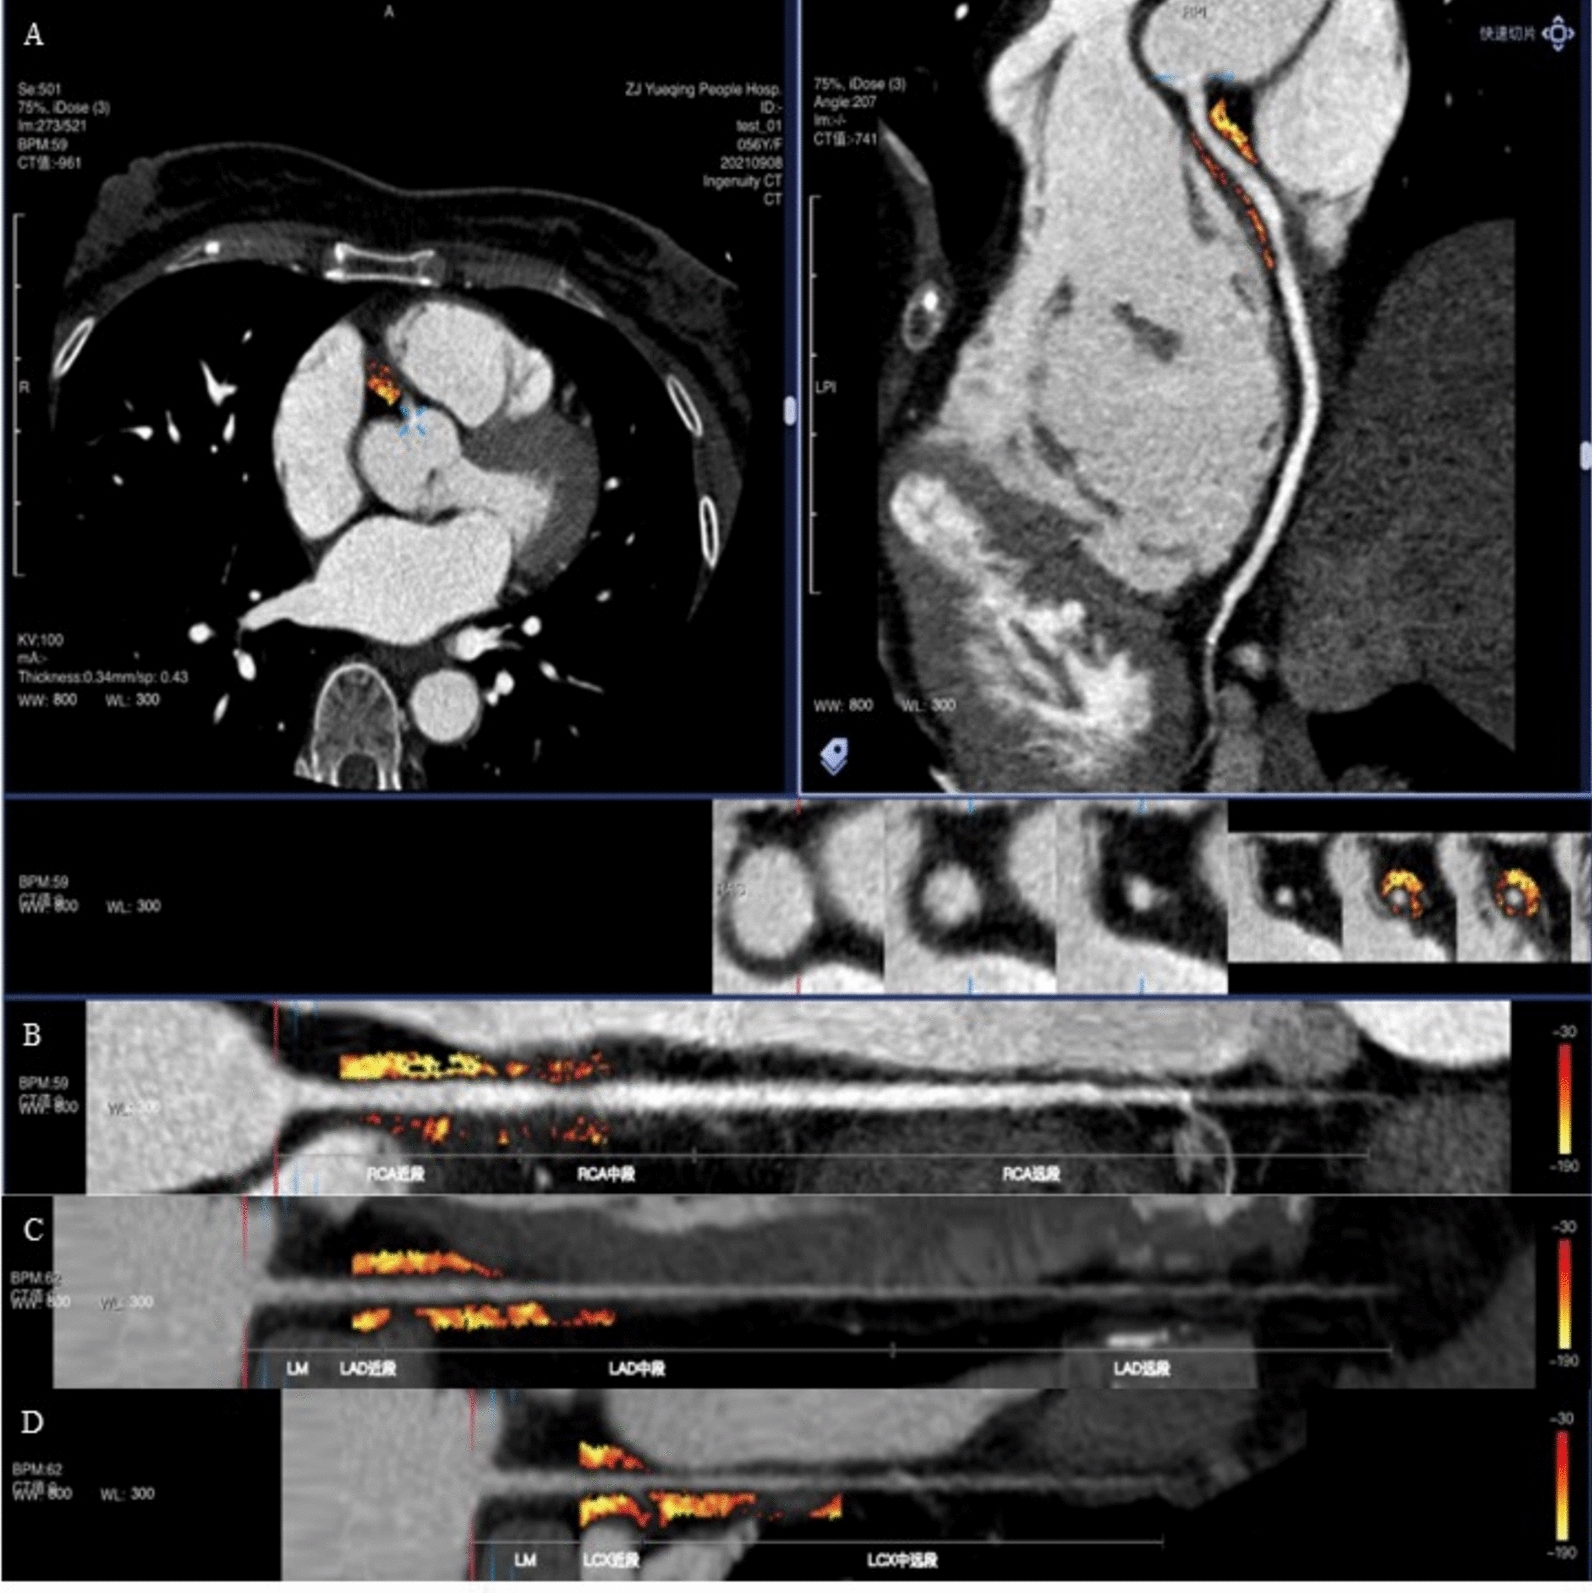

Methods: This study retrospectively enrolled 686 hospitalized T2DM patients from four branches of Guangdong Provincial Hospital of Chinese Medicine between January 2017 and December 2021. PCAT-FAI and volume index were measured using coronary CTA. Major adverse cardiovascular events (MACE) were recorded during follow-up. Eight machine learning algorithms were applied, and multiple evaluation metrics were used to compare the predictive performance of the models. Feature contributions in the best-performing model were interpreted using both feature importance ranking and SHapley Additive exPlanations (SHAP) values.